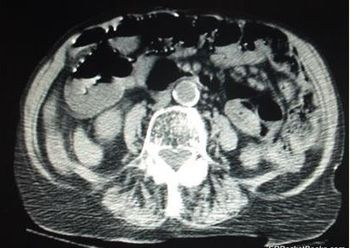

The patient has had 10 episodes of bleeding in the past 24 hours. Can you find clues to the underlying problem in the history and on the CT scan?